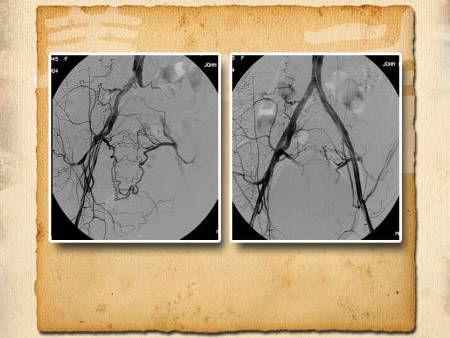

看看電視劇泡泡腳,是很多老年人的習(xí)慣。但是并不是所有的人都適合泡腳,比如下肢動脈血管有堵塞的人。另外,高血壓、心臟病的患者不要長時間的用溫度過高的水泡腳,對身體也不好。敬請收看由中日友好醫(yī)院心外科主任劉鵬教授主講的《從血管看壽命—2》。

腿部血管堵塞,可能會在走路時候,走著走著腿就感覺疼、沉,要停下來休息休息。另外,如果發(fā)現(xiàn)自己的趾甲增厚、腿毛變少,也可能是腿部血管堵塞的表現(xiàn)。自己的感覺只能是初步判斷,那去醫(yī)院做什么檢查能發(fā)現(xiàn)自己的腿部血管有沒有堵塞呢?更多具體內(nèi)容請收看本期節(jié)目。

足背動脈很好找,在節(jié)目中也給大家介紹過多次。(位置如圖)足背動脈摸不到或者搏動很弱的人可能就是足背動脈有堵塞了。那這條動脈堵了,腿部供血就該有問題了吧?是不是就要去醫(yī)院做手術(shù)了呢?也不一定。因為在我們腿上還有其他動脈血管存在,一條堵了,還有其他的血管能彌補已經(jīng)堵塞的足背動脈的不足,那還能摸摸哪兒自查其他血管好不好呢?更多具體內(nèi)容請收看本期節(jié)目。